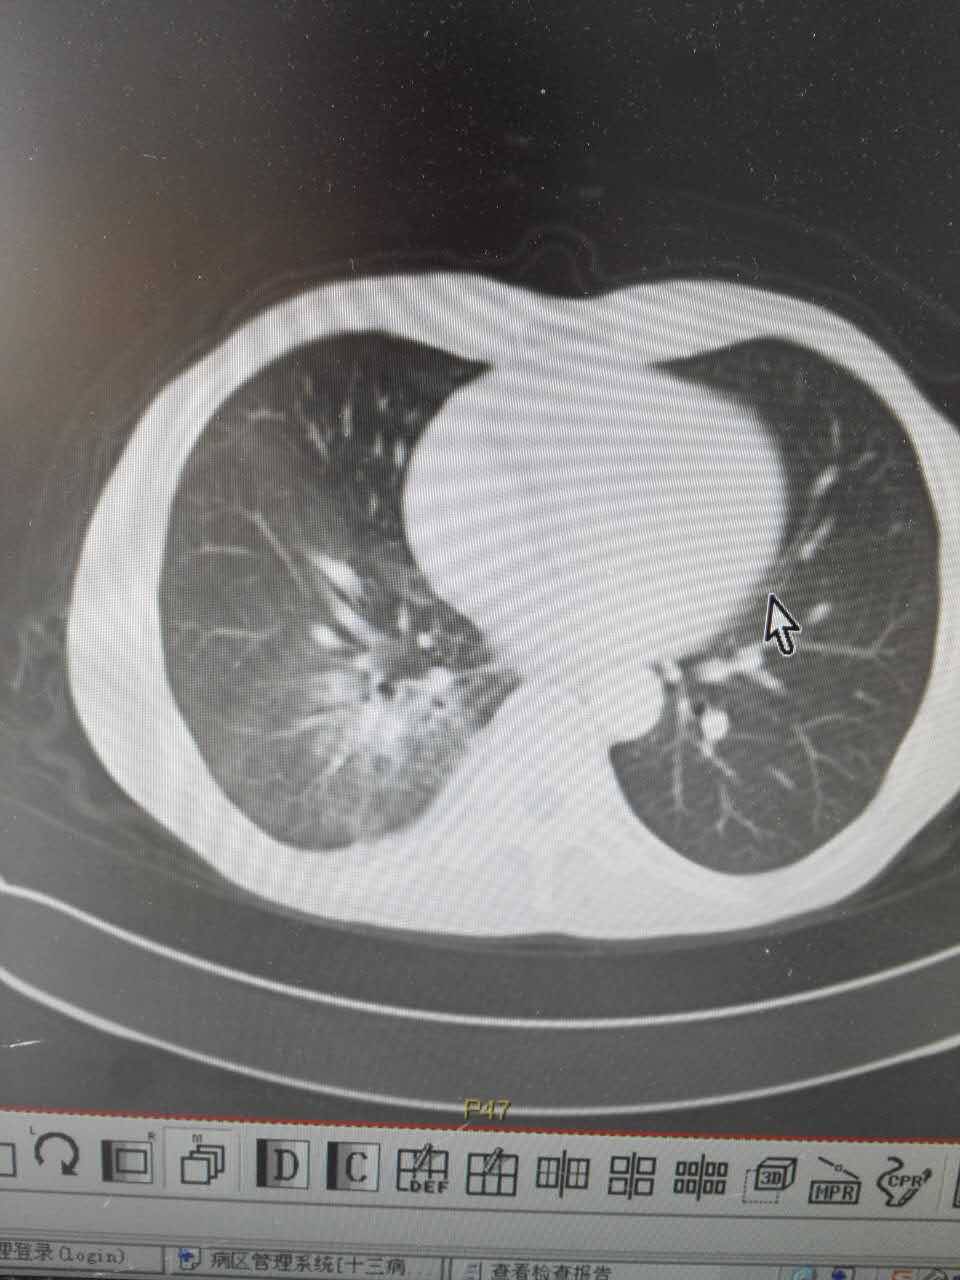

父亲增强CT报告出来了,医生说不是很好(吃克唑替尼才两个多月)

肺部一片一片白色信号,医生说已经看不出来原病灶大小了,说是阻塞性肺炎,该怎么治疗?

颈部淋巴结和肝转症状消失了